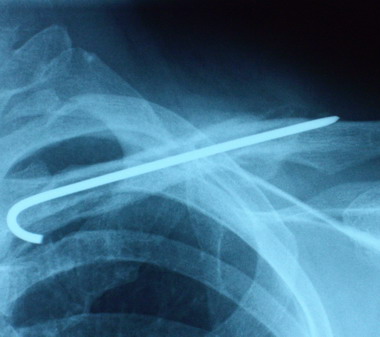

4月30日に診察へ行ったときの骨の状態は

泣きたくなるほどの微妙な骨の再生やってんけど

今日診察へ行ってきたら

ほぼ完治に近い状態まで骨は再生されてました。

骨って一旦再生が始まると成長が早いのでしょうか。

前回の骨の画像が分かりにくかった感じがしたので

今回は4月30日と今日の画像を並べてみます。

骨は引っ付いても左右の肩の幅は若干違いもありますし

肩も下がってます。

それに、今まで腕を肩以上上げることを禁じられてたので

肩こりだと思うんですが、今でも肩が『痛い』と言ってます。

これからは腕も体も自由に動かして肩こりと運動不足を

解消してもらおうと思います。

まぁ、きっと我が家のおいやんならこの先も

どこかしこ『痛い 痛い』と言い続けるでしょうけどね。( ̄ェ ̄;)

骨折をした時は、幼稚園の女の子相手のケンカでも負けるんちゃうか?

って言うくらい鎖骨と肩を大事に大事に守ってたけど

今度の診察でワイヤーともおさらばだそうです。

とりあえず、長い長い鎖骨骨折物語は無事完結です。

骨折治療期間 王子 ほぼ1ヶ月。 おいやん 約3ヶ月。

痛い 痛いと言った数 王子 少数。 おいやん 言いすぎ。

治療費 約1万 おいやん 約10倍くらい(使いすぎ。)